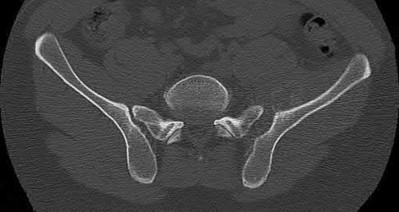

Which of the following images shows an injury pattern most consistent with a lateral compression type 3 pelvic ring injury?

Figure C is an axial CT scan of a lateral compression type 3 (LC3) pelvic ring injury.

Classically, LC3 injuries demonstrate an ipsilateral lateral compression and a contralateral APC (windswept pelvis) fracture pattern. The most common mechanism of injury in these cases is a rollover MVC or pedestrian vs. auto. LC1 injuries are characterized by an oblique or transverse ramus fracture and ipsilateral anterior sacral ala compression fracture, while LC2 injuries consist of a rami fracture and ipsilateral posterior ilium fracture dislocation (crescent fracture). While LC1 injuries can often initially be managed conservatively with protected weight-bearing and close observation, LC2 and LC3 pelvic ring injuries are almost universally operative.

Answer 1: This represents a lateral compression type 2 injury. Answer 2: This represents a lateral compression type 1 injury.

Answer 4: This represents an anterior posterior compression type 2 injury. Answer 5: This represents an anterior posterior compression type 3 injury.